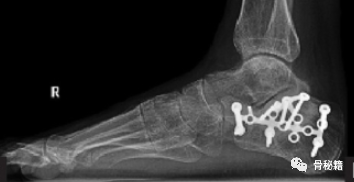

3.Broden位片 可评估跟距后关节面的较好方法,用于术中评估关节面骨折复位情况;

距下关节的可视化最好通过侧斜视图获得, 其中 C型臂向后滚动约30 度,稍微向床脚倾斜。可以通过不同的旋转和倾斜量进⼀步微调后⼩⾯和距下关节可视化。

透视装置与床脚成45 度⻆时,外科医⽣将透视装置向后滚动到桌⼦⻆下⽅的⽔平位置,即可轻松查看后⾜视图(Harris视图)